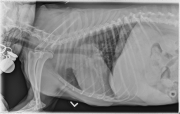

Today’s case is a 13-year-old Fox terrier with increased respiratory rate on excitement or in lateral recumbency. What are your findings?

On both lateral projections, there is increased soft tissue opacity in the cranial thorax, cranial to the hilus of the lungs and projecting dorsal to it on the left lateral projection. On the dorsoventral projection, the mass is located more in the left hemithorax and displaces the trachea to the right. The vasculature to the cranial lung lobes appears small, and the left caudal lobar arteries and veins are less visible than the right. In the portion of the abdomen included, the liver is enlarged. There is a diffuse bronchointerstitial pattern throughout the lungs. In the portion of the abdomen included, the liver is enlarged.

Differential diagnoses for the origin of the thoracic mass include the left cranial lung lobe, the mediastinum, or less likely the thoracic wall. The central location of the mass on both lateral projections suggests a dorsal mediastinal origin, however this should be confirmed with thoracic ultrasonography or echocardiography. The location is less typical of a ventral mediastinal mass such as thymoma. The small pulmonary vessels may suggest compression of the pulmonary artery by the mass. The diffuse bronchointerstitial pattern may be inflammatory or fibrotic in nature.

Thoracic ultrasonography and echocardiography were performed and the mass was seen to originate in the region of the aortic arch and surrounded the main pulmonary artery. A fine needle aspirate was non-diagnostic. Differential diagnoses included chemodectoma and ectopic thyroid carcinoma.